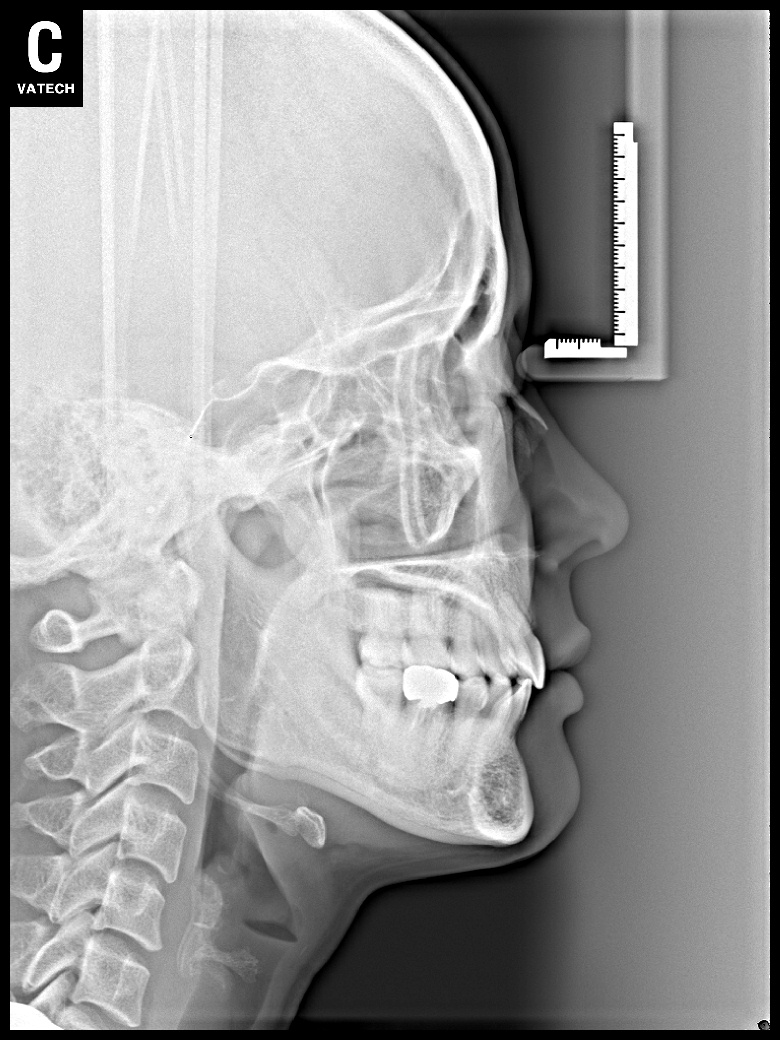

치료 전 사진입니다.